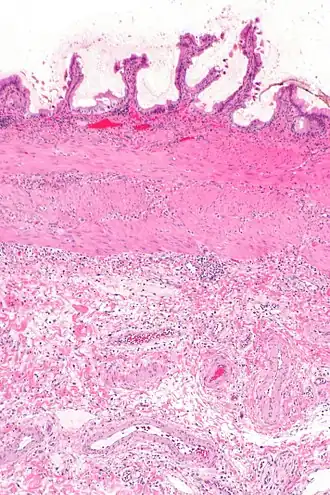

La cholécystite est l'inflammation de la vésicule biliaire.

La cholécystite est liée à l'infection du liquide vésiculaire, suite le plus souvent à l'obstruction du canal cystique par un calcul biliaire : le liquide en stase, d'abord stérile, provoque une inflammation locale qui peut se surinfecter alors, le plus souvent avec des germes digestifs présents dans le duodénum. Si elle n'est pas prise en charge convenablement, la vésicule biliaire peut se gangréner et provoquer une péritonite.

Cholécystite chronique